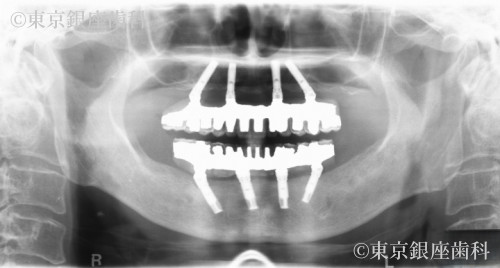

Before

施術内容 ワンデイインプラント

重度歯周病で上下インプラント治療を実施。術後に皮膚の湿疹・赤みが出たが、チタンアレルギーではなく経過観察で改善。現在も問題なく使用できている。

上下ワンデイインプラント